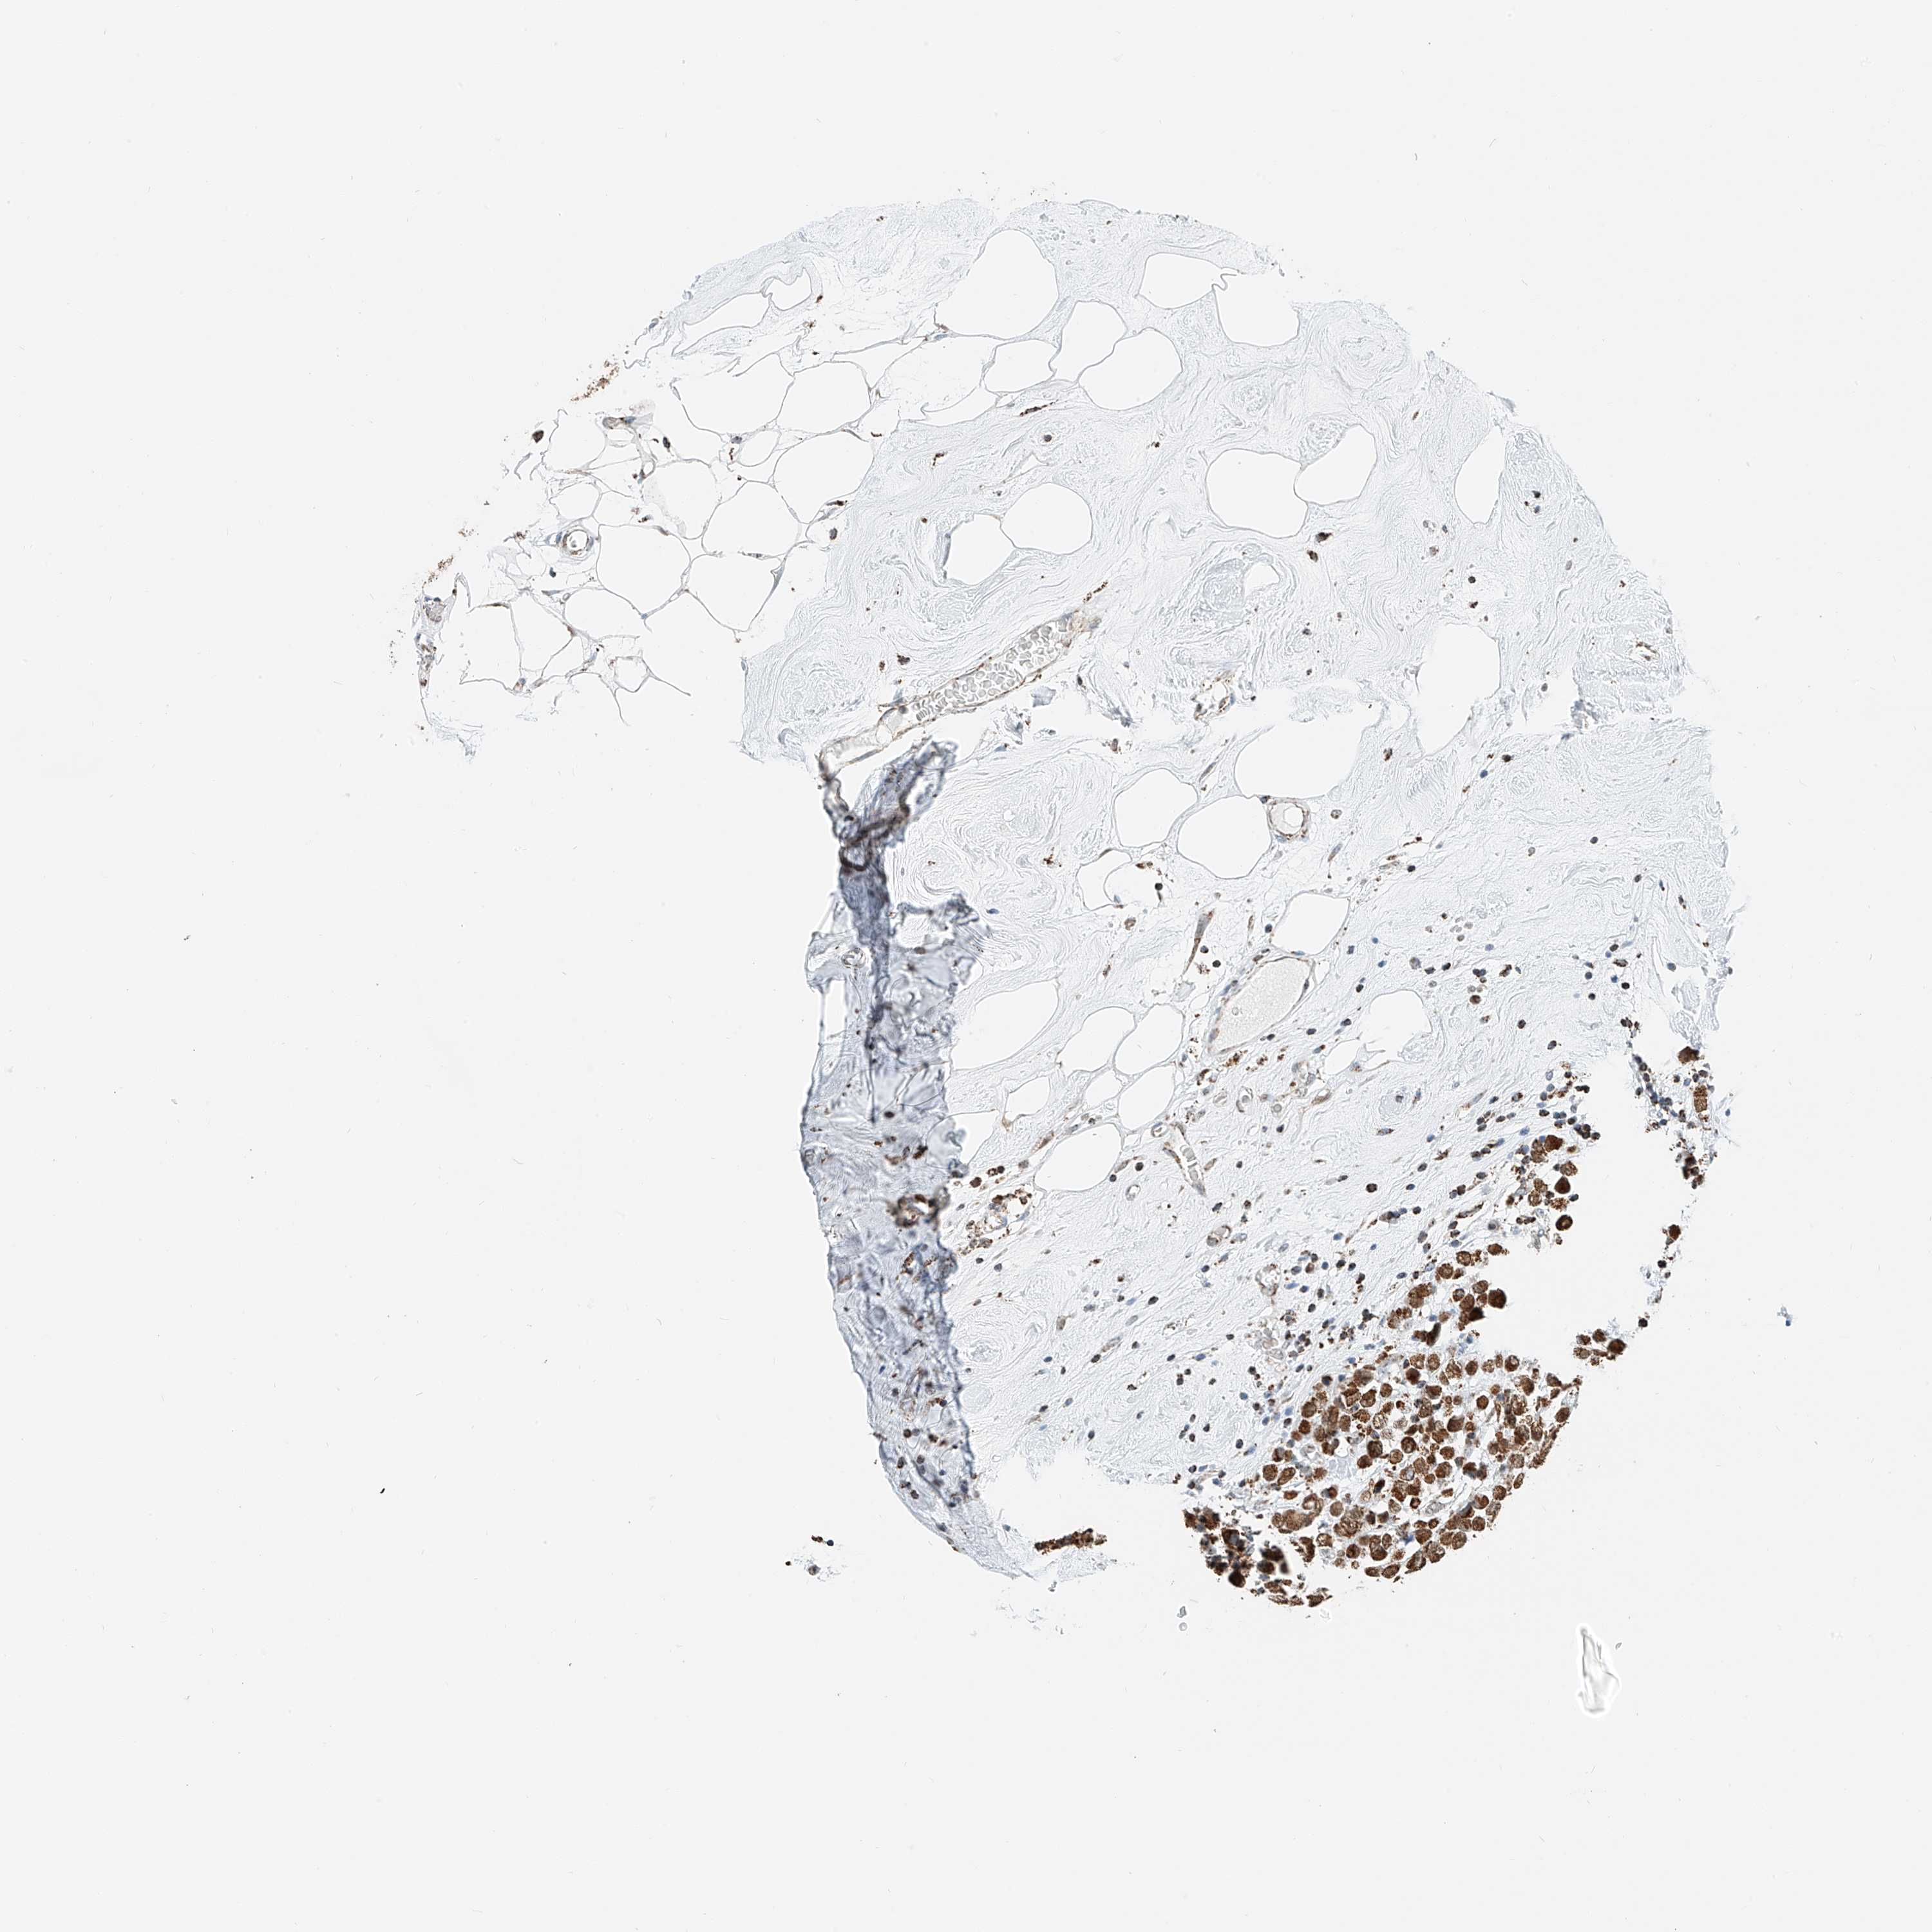

BRCA TCGA BRCA VALIDATION PROTEIN EXPRESSION

ANTIBODIES

AND

VALIDATION